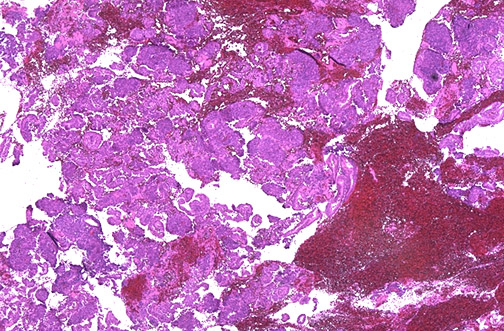

| This is menstrual phase endometrium with breakdown of the glands and stroma, along with hemorrhage and leukocyte infiltration. The upper two-thirds of the endometrium is shed. From lower third, the basalis layer, which does not respond to the ovarian hormones, will arise a new endometrial lining in the next cycle. |